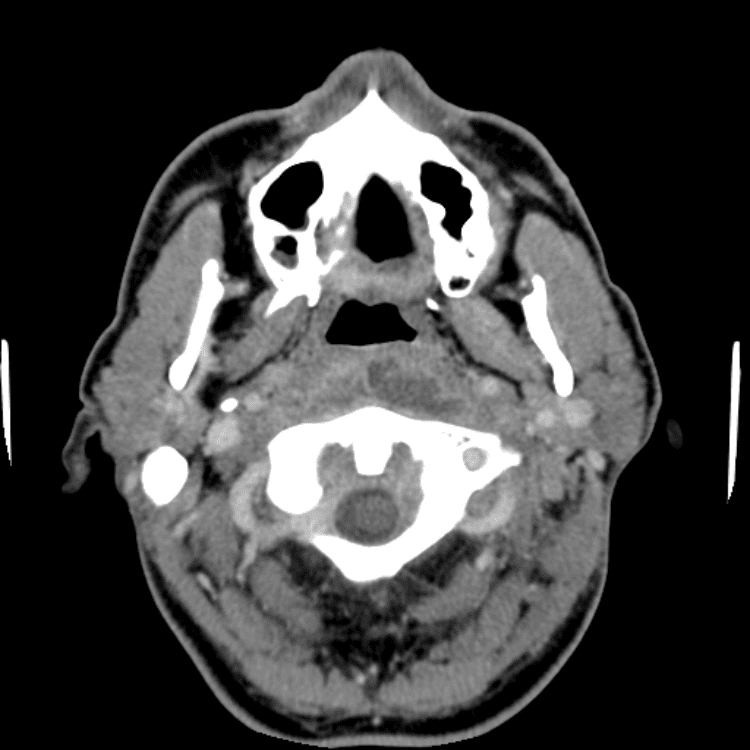

Head and Neck

Simulates call by including subtle or difficult cases and some normals.

27 cases